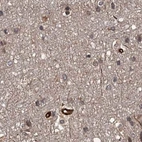

Immunohistochemical staining of human cerebral cortex, colon, fallopian tube and testis using Anti-RPAP3 antibody HPA038312 (A) shows similar protein distribution across tissues to independent antibody HPA038311 (B).